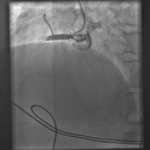

Angiografia mostrando a artéria coronária direita obstruída

Do acervo pessoal do Dr. Mahi Ashwath; usado com permissão